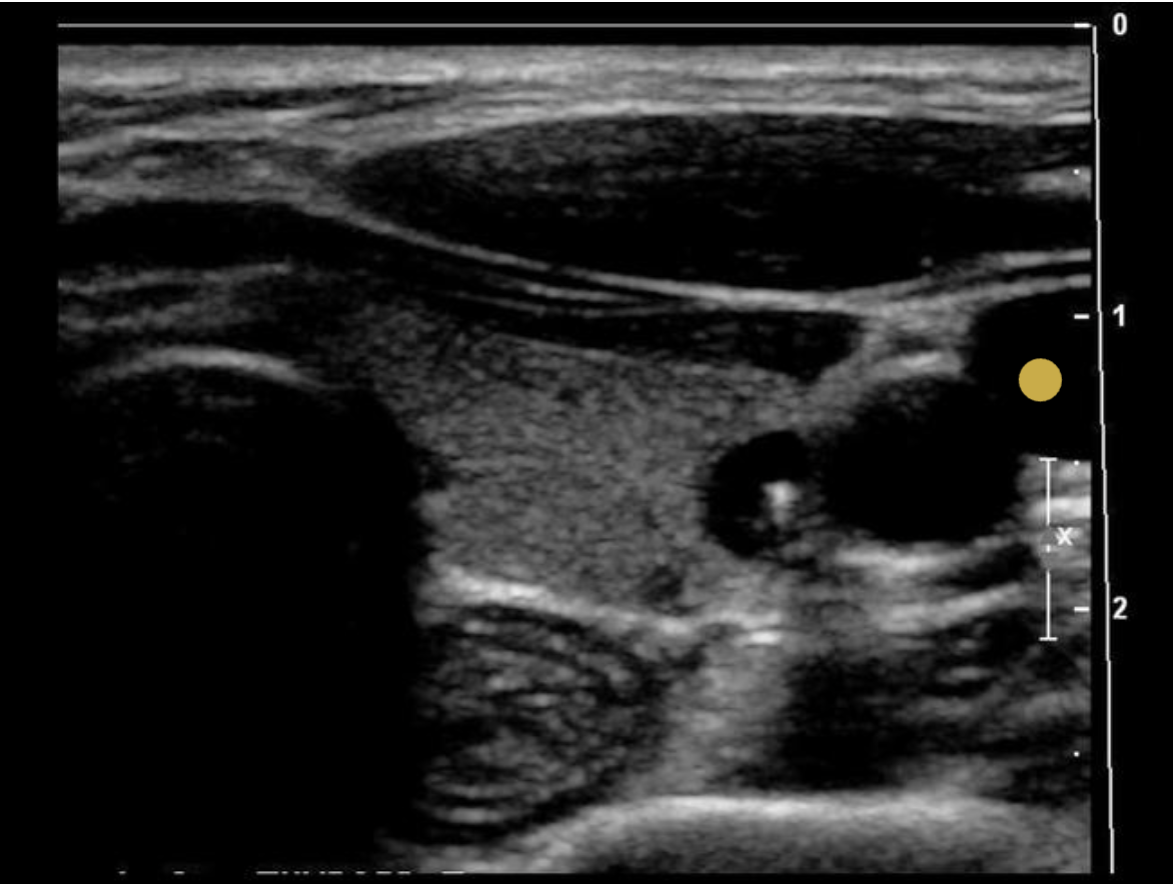

Find the mediastinum testis

The mediastinum testis is an infolding of the tunica albuginea that enters the posterior testicle. Blood vessels and tubules enter and exit the testicle through the mediastinum. testis. and it can be considered the hilum of the testicle.

What structure is indicated by the arrow?

D. mediastinum testis

Folds of the tunica albuginea form sections within the testes that converge at a single location called the mediastinum testis (similar to a hilum). The rete testes is a series of channels within the mediastinum. Blood vessels and ductules enter/exit the testicle at the mediastinum.